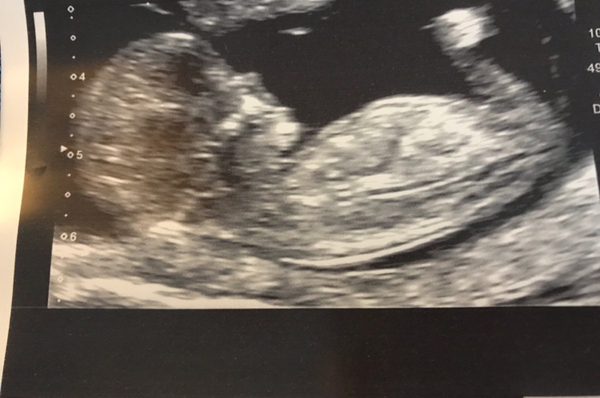

This was my scan yesterday, now due 30th Aug so I'm now only 12 weeks today! How do I join the fb group?